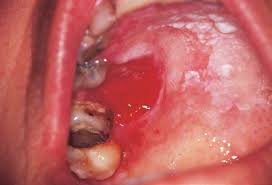

3. Tompok putih atau merah di dalam mulut

Image result for red spotted in human mouth